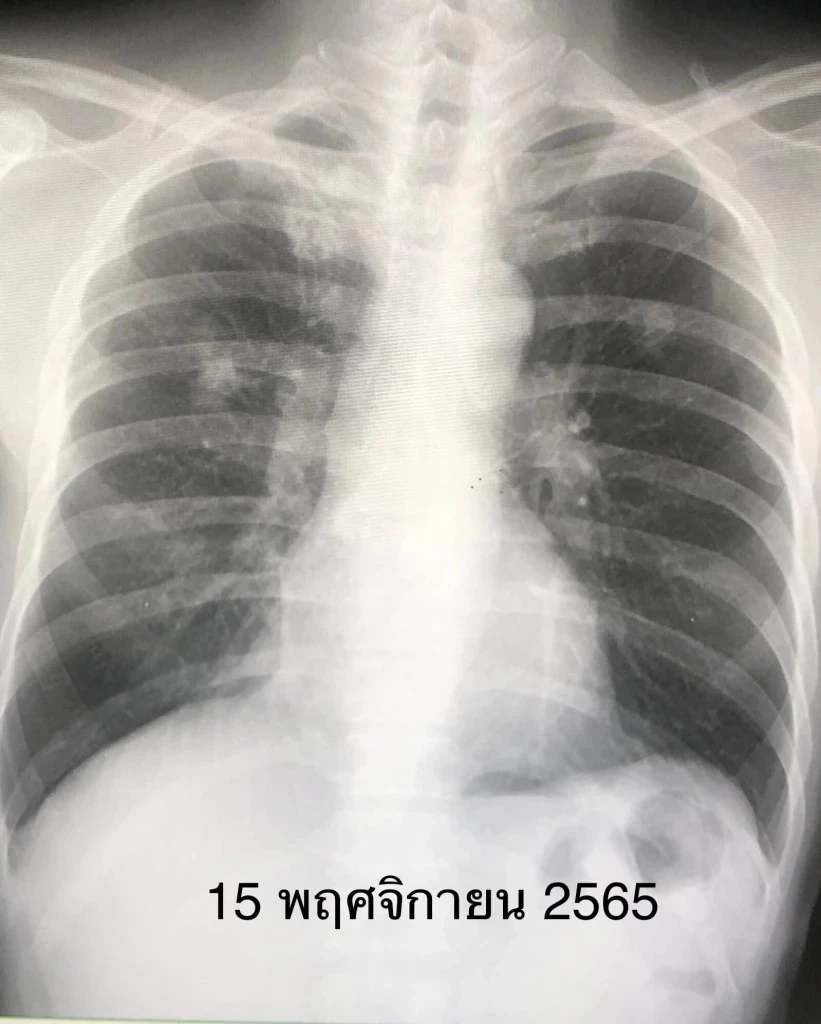

ตรวจร่างกาย ผอมลง เอกซเรย์ปอดมีฝ้าขาวทั้ง 2 ข้าง (ดูรูป) เอกซเรย์ปอดครั้งก่อนวันที่ 18 กุมภาพันธ์ 2563 ปกติ (ดูรูป) ทำคอมพิวเตอร์ปอดเห็นฝ้าขาวทั้งปอดซ้ายและปอดขวา (ดูรูป) ค่ามะเร็ง CEA ในเลือดสูง 7.4 เจาะชิ้นเนื้อจากปอดด้านซ้าย ส่งตรวจไม่พบเชื้อวัณโรค ไม่พบเชื้อรา ตรวจทางพยาธิวิทยา พบเป็นมะเร็งปอดชนิด adenocarcinoma